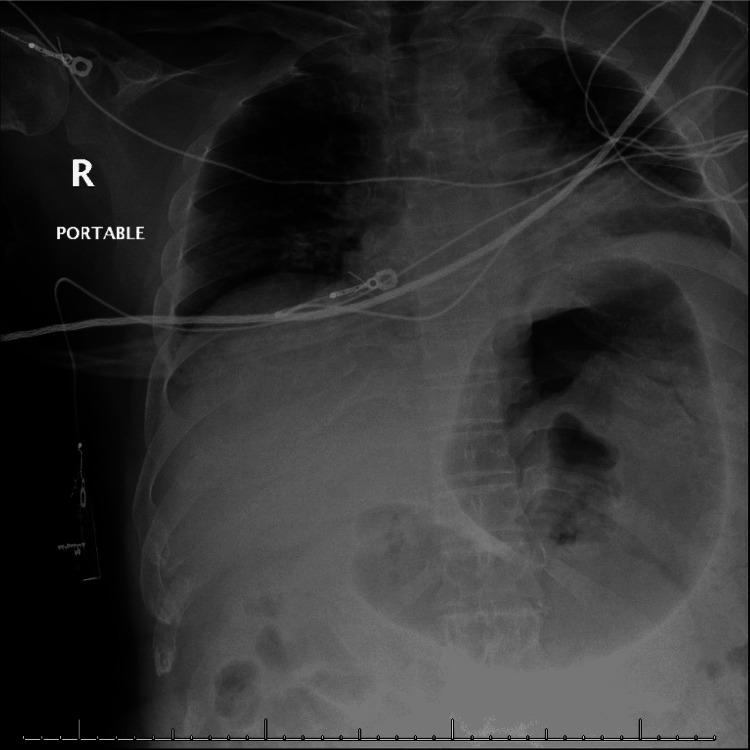

Patients with achondroplasia often present with anatomical abnormalities and altered cardiopulmonary physiology that significantly increase their perioperative risk for cardiovascular and respiratory complications (e.g., worsening ventilation-perfusion mismatch, imminent desaturation, difficult airway). We describe a 34-year-old achondroplastic male presenting with altered mentation following a traumatic subdural hematoma that necessitated emergent craniotomy evacuation. Initial attempt at intubation was complicated by rapid desaturation and bradyarrhythmia. Subsequently, the patient went into cardiac arrest requiring cardiopulmonary resuscitation. A laryngeal mask airway (LMA) was secured and fiberoptic intubation was achieved in succession. Following return of spontaneous circulation (ROSC), a repeat CT scan showed the subdural hematoma to be stable in size and neurosurgery opted to delay his surgery for conservative management and close monitoring. This case highlights the unique airway challenges and anesthetic considerations in management of achondroplastic patients.

软骨发育不全患者常伴有解剖结构异常和心肺生理改变,这显著增加了他们围手术期发生心血管和呼吸并发症的风险(如通气/血流不匹配加重、即将出现的血氧饱和度下降、气道困难)。我们描述了一名34岁的软骨发育不全男性患者,因创伤性硬膜下血肿导致意识改变,需要紧急开颅血肿清除术。初次插管尝试因血氧饱和度迅速下降和心律失常而变得复杂。随后,患者发生心脏骤停,需要进行心肺复苏。成功置入喉罩气道(LMA)并相继完成纤维支气管镜插管。自主循环恢复(ROSC)后,重复CT扫描显示硬膜下血肿大小稳定,神经外科选择推迟手术,进行保守治疗和密切监测。该病例突出了软骨发育不全患者气道管理中独特的挑战和麻醉注意事项。